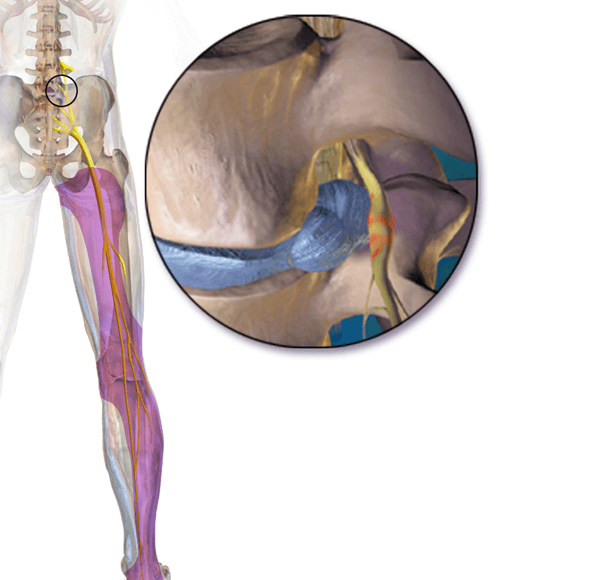

Cuando se produce una hernia puede ocurrir que se compriman alguna o varias de las estructuras nerviosas que se encuentran a este nivel. El síntoma principal que vamos a tener es una ciática.

Una ciática es un dolor irradiado que desciende por la cara posterior del muslo y sigue por la pierna hasta el pie. Habitualmente se asocia con debilidad y trastornos de la sensibilidad. A nivel del segmento L5-S1 podemos tener afectadas la raíz L5 la raíz S1 y el saco dural, pudiéndose afectar más de una estructura nerviosa a la vez según el tamaño de la hernia o la estrechez del canal lumbar.

Síntomas L5: La raíz L5 a nivel de L5-S1 se puede afectar por hernias laterales, que no tienen por qué ser muy grandes ya que muchas veces tenemos asociada una estrechez del agujero de conjunción (recuerda que la raíz L5 sale de la columna por el agujero que forman las vértebras L5 y S1). La raíz L5 también se puede ver afectada por hernias centrales más voluminosas. La clínica provocadas por la compresión de la raíz L5 por una hernia discal L5-S1 es una ciática que discurre por la nalga y baja por la cara posterolateral del muslo, cara lateral de la pierna y dorso del pie. Muchas veces tienen asociada debilidad para ponerse de talones.

Síntomas S1: En este caso tendremos un dolor irradiado por la nalga, cara posterior del muslo que desciende por la cara lateral de la pierna y el pie. Notaríamos debilidad para doblar los dedos del pie y ponernos de puntillas y el área con sensibilidad alterada sería la cara externa de la pierna y el pie. La raíz S1 es responsable del reflejo aquíleo que lo tendríamos disminuido.